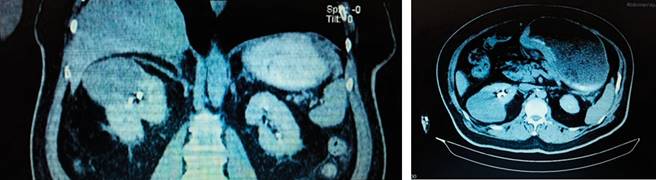

Se trata de un paciente masculino de 68 años, con antecedente de diabetes mellitus tipo 2, tabaquismo y etilismo crónico por más de 20 años. Niega antecedentes quirúrgicos. Inicia padecimiento al presentar cuadros intermitentes de distensión abdominal, dispepsia, disfagia progresiva de sólidos a líquidos. Niega pérdida de peso o datos de sangrado de tubo digestivo. Se inicia protocolo de estudio con tomografía axial computarizada con contraste intravenoso reportando tumor renal derecho de 7 x 6 x 4 cm de bordes redondeados, definidos, heterogénea, centro hipodenso en relación con degeneración quística o necrótica (Figura 1); presentando signo de la garra tras la administración de contraste intravenoso, con realce en 20 UH, con fase trifásica retardada, realce de la lesión con 10 UH; se observa estómago distendido, engrosamiento de la mucosa antral y pilórica de 1.7 cm, no se observan metástasis hepáticas ni a distancia en la tomografía. Se realiza panendoscopia que muestra neoplasia gástrica infiltrante (adenocarcinoma Borrmann II) (Figura 2). El resultado histopatológico de la biopsia gástrica reporta: adenocarcinoma poco diferenciado infiltrante difuso de células en anillo de sello. El marcador CA 19-9 con valores de 126 U/ml con estatificación clínica del cáncer gástrico. Se lleva a cabo la intervención quirúrgica con gastrectomía total, linfadenectomía D1, esofagoyeyuno-anastomosis con engrapadora circular de 29 mm y enteroentero-anastomosis-latero-terminal con engrapadora lineal 55 mm en Y-de-Roux (Figuras 3 y 4 ). Durante el mismo procedimiento quirúrgico se realiza nefrectomía radical derecha con los siguientes hallazgos: líquido libre cetrino escaso, riñón derecho con tumor sólido en polo superior de 10 x 5 cm, vena renal sin trombo; estómago con tumor en la curvatura menor, antro y píloro, extensión del tejido tumoral hacia tronco celíaco, incluyendo arteria gástrica izquierda, arteria hepática hasta la gastroduodenal. Tumor en cara posterior de estómago con adherencia a cuerpo de páncreas, implantes tumorales en mesocolon transverso cerca del ángulo de Treitz, adenomegalias en epiplón mayor, unión esofagogástrica sin actividad tumoral. Con estatificación de T4aN2M0 del cáncer gástrico, el cáncer renal con estatificación de T2bN0M0. Paciente cursó con buena evolución postquirúrgica, sin datos de fuga de anastomosis, toleró la vía oral y deambulación al quinto día postquirúrgico y con mejoría clínica, por lo cual se decide su egreso en su séptimo día de estancia.

Figura 1: Tomografía Axial Computarizada muestra abdomino pélvico contrastado de cortes axial y coronal donde se observa tumoración renal con datos intermedios de malignidad, estómago con gastroparesia, así como engrosamiento de mucosa antral y pilórica.